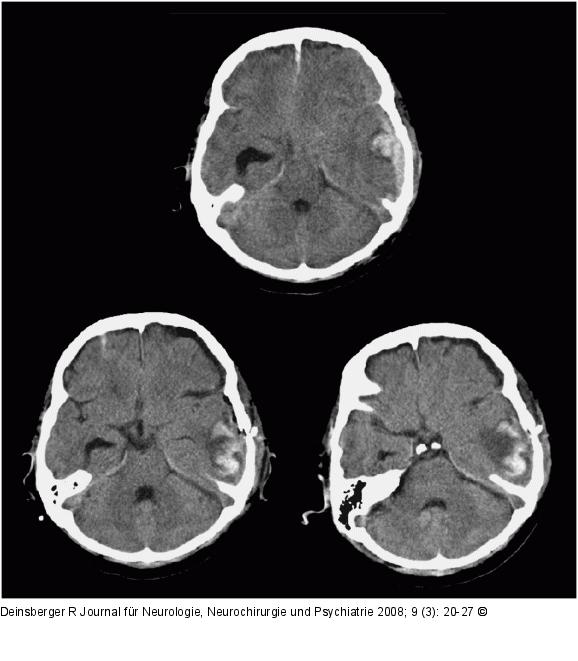

Abbildung 3: Kontusionsblutung

Verlauf einer Kontusionsblutung akut, 24 und 72 Stunden nach Trauma |